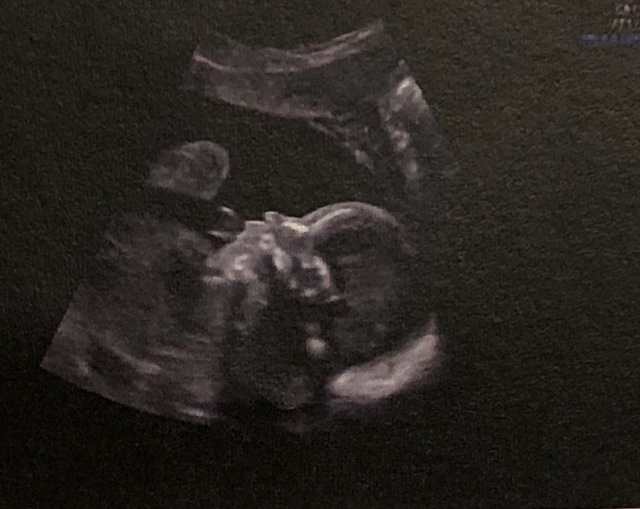

宝宝3个月12天

孕23周+5天